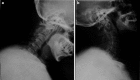

Methods: A 49-year-old Chinese male presented with a progressive cervical myelopathy (C-JOA score 11 immediately pre-op). Segmental OPLL at the C2-3 disk space was visible, together with invagination of the bilaterally hypoplastic C2 lamina into the spinal canal. Signal abnormalities of the spinal cord were evident on both T1 and T2 sequences.

Results: The patient underwent a posterior decompression and instrumented fusion at C2-3 using pars screws at C2 and lateral mass screws at C3. Following surgery there was a rapid and significant improvement in the neurological symptoms, with the C-JOA score improving to 14 at final follow-up. A successful fusion was evident.